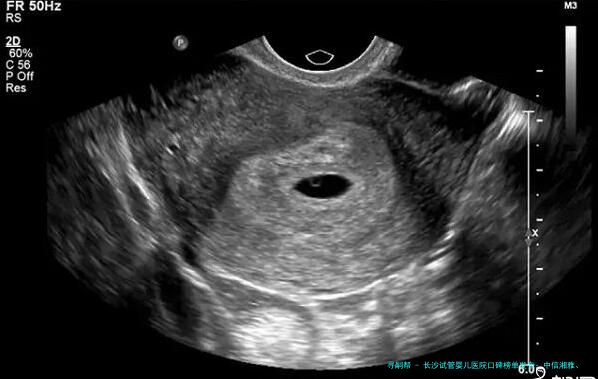

至于众多在长沙及附近地区,正面临“原因不明性不孕”困扰的夫妇来说,选择一家技术靠得住、名誉优胜的试管婴儿医院,是迈向新生命盼望的重要一步。网络上信息繁杂,怎样扒开迷雾,寻到真正合适自己的选择?今日,我们就来透彻聊聊长沙地区在辅助生殖范围颇具口碑和力量的几家医院,并提供一些抉择时的重要考量点。

在辅助生殖领域,医院的综合力量、实践室水平、医生经验以及个性化的诊疗方案都至关重要。下列是根据医院资质、技术领域、病人口碑等多维度综合评估后,在长沙区域备受留意的5家医疗组织。